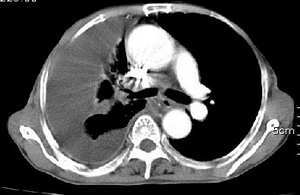

右肺毁损萎陷,其内可见钙化灶、残存空腔及支气管影。左上叶可见多发小结节影。纵隔左移,其内未见肿大淋巴结。右侧胸腔大量积液。考虑:肺结核并右肺毁损;右侧胸腔大量积液。

右侧大量胸腔积液伴右肺压迫性肺不张,上叶内是不是结核灶?

右侧大量胸腔积液伴右肺压迫性肺不张,左上叶结核.

包裹性积液,并右侧肺不张